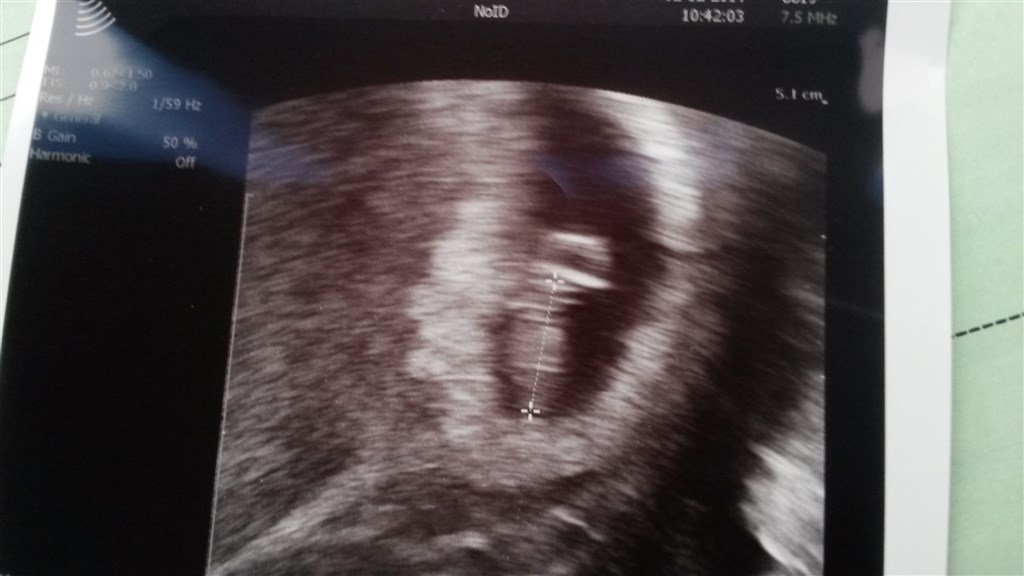

Så blev jeg scannet idag. Blev sat 3 dage tilbage så er nu 7+0.

den lille spire er omkring 8 mm og hjertet slår så fint

Vedhæftede fotos (klik for at se i fuld størrelse)